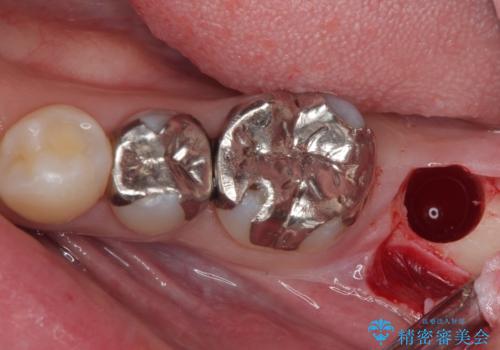

- 奥歯を抜歯してから放置しているとのことで来院された患者様です。

歯が割れて抜歯になってしまったとのことで、咬合力に抵抗できるよう、インプラントによる補綴治療を行うこととしました。

長い期間歯が欠損していた下顎奥歯に、インプラント埋入と同時に仮歯を装着すると(埋入即時荷重インプラントを行うと)、舌の付け根で仮歯を横向きに押してしまい、インプラントが脱落する危険性が高くなります。

インプラント埋入時に、装着できる状態の仮歯を用意するものの、埋入後すぐには加重させず、インプラントが無事に生着したことを確認した後に装着することで、危険を回避しつつ外科処置や痛みの少ないスムーズな治療を行うことができます。